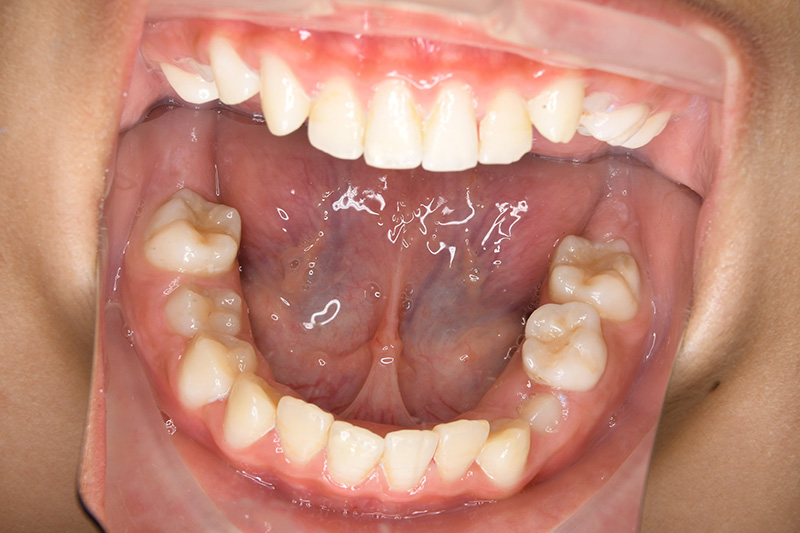

| 口腔内所見 | over jet 2.5mm、over bite 2.0mm、右側大臼歯関係はEnd on class Ⅱ、上顎左側Eは早期喪失により左側大臼歯関係はFull classⅡ、右側Eは6の異所萌出により歯根吸収が進行したため一般歯科医院にて抜去済みであった。 |

| パノラマ所見 | 上顎両側6、特に左側6は近心傾斜が認められ、両側5の萌出スペース不足が認められた。 |